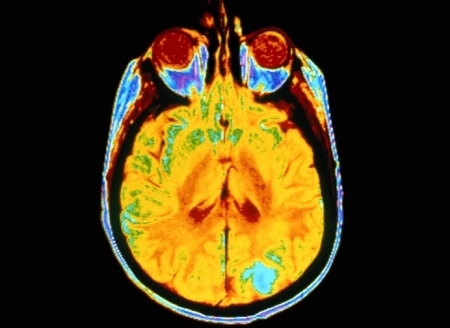

Pesquisadores da Universidade Brigham Young (BYU), dos Estados Unidos, observaram o cérebro de mulheres saudáveis por meio de ressonância magnética e identificaram a sensação do medo quando elas enxergavam imagens de outras mulheres com sobrepeso.

O grupo de mulheres avaliado não tem histórico de distúrbios alimentares, por isso apresentavam pouca probabilidade de ter problemas com a imagem corporal. Mas, quando eram expostas a imagens de mulheres com sobrepeso, o cérebro ativava uma parte que processa a identidade e a autorreflexão. Homens colocados na mesma situação não apresentaram nenhuma reação.